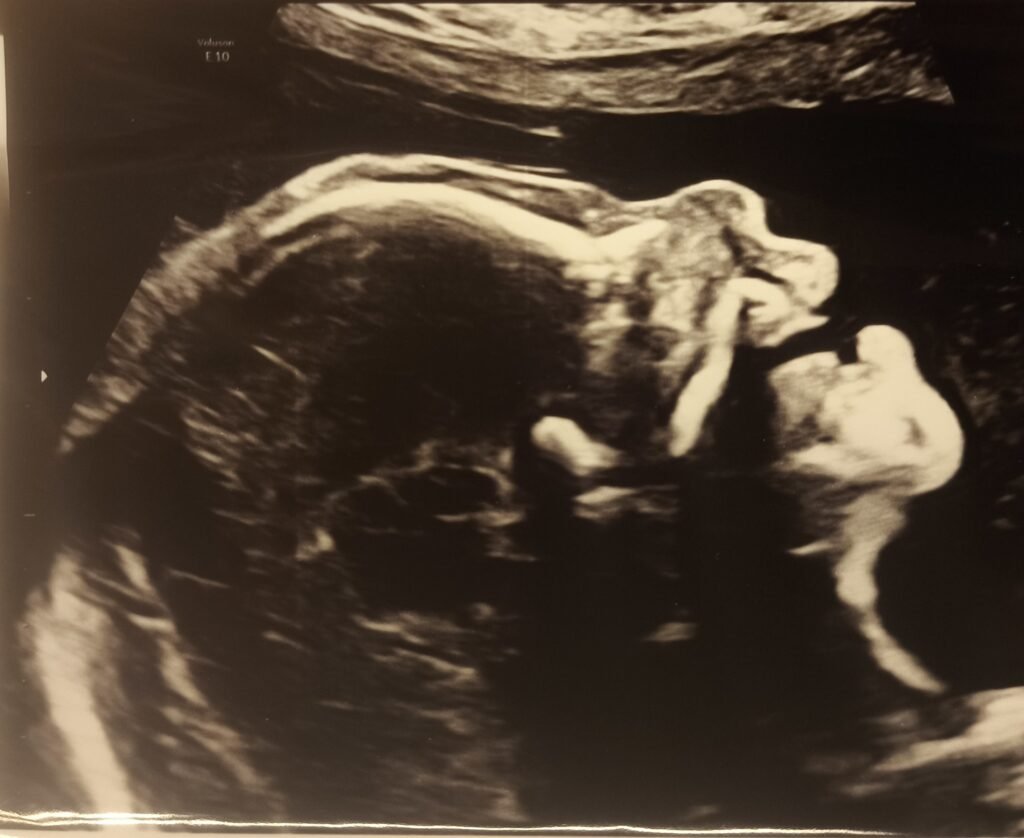

Anatomy scan – Week 20

04/11/2025

We are halfway. Time for another ultrasound. If you assume, half baked is half a baby you are sorely mistaken. During the 20-week scan we got to see organs, bones, blood flow through the heart and umbilical chord and so far everything looks as it should. The face profile shows us the cutest button nose and we can’t wait to meet our little munchkin. In the picture you can see the right foot.

Healthy baby, happy parents (for now…)